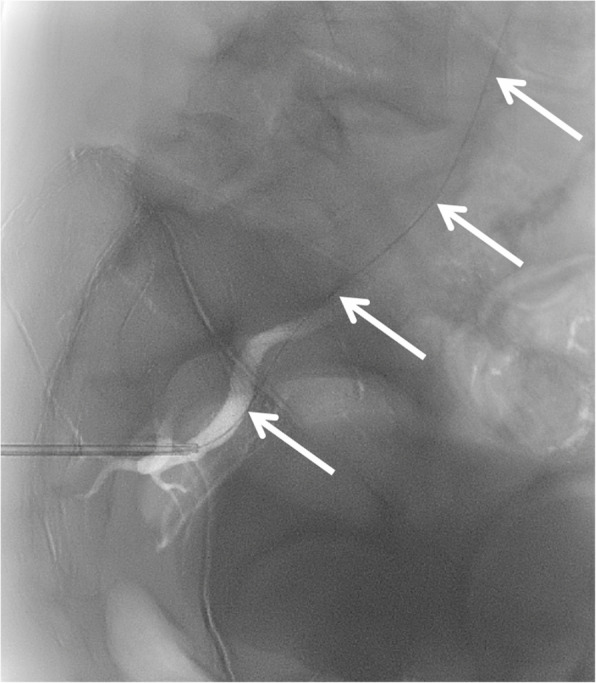

Background: Iatrogenic superior gluteal artery injury (SGA) following bone marrow biopsy is rare but potentially life-threatening. Due to the deep intrapelvic location of the vessel, conventional management with manual compression or surgical repair is challenging. Traditional management via endovascular coil embolization requires arterial access and vessel sacrifice. Case presentation We present a case of SGA injury resulting from a bone marrow biopsy in a patient with suspected T-cell lymphoma. The injury was successfully managed using a 6 french Angioseal closure device applied directly through the biopsy puncture site in the gluteal region, with the patient maintained in the lateral decubitus position. The approach achieved immediate hemostasis while preserving arterial patency.

Conclusion: This represents the first reported use of an Angioseal device for direct percutaneous treatment of iatrogenic SGA injury. This technique offers an effective hemostasis and vessel preservation, expanding the interventional radiology's armamentarium.